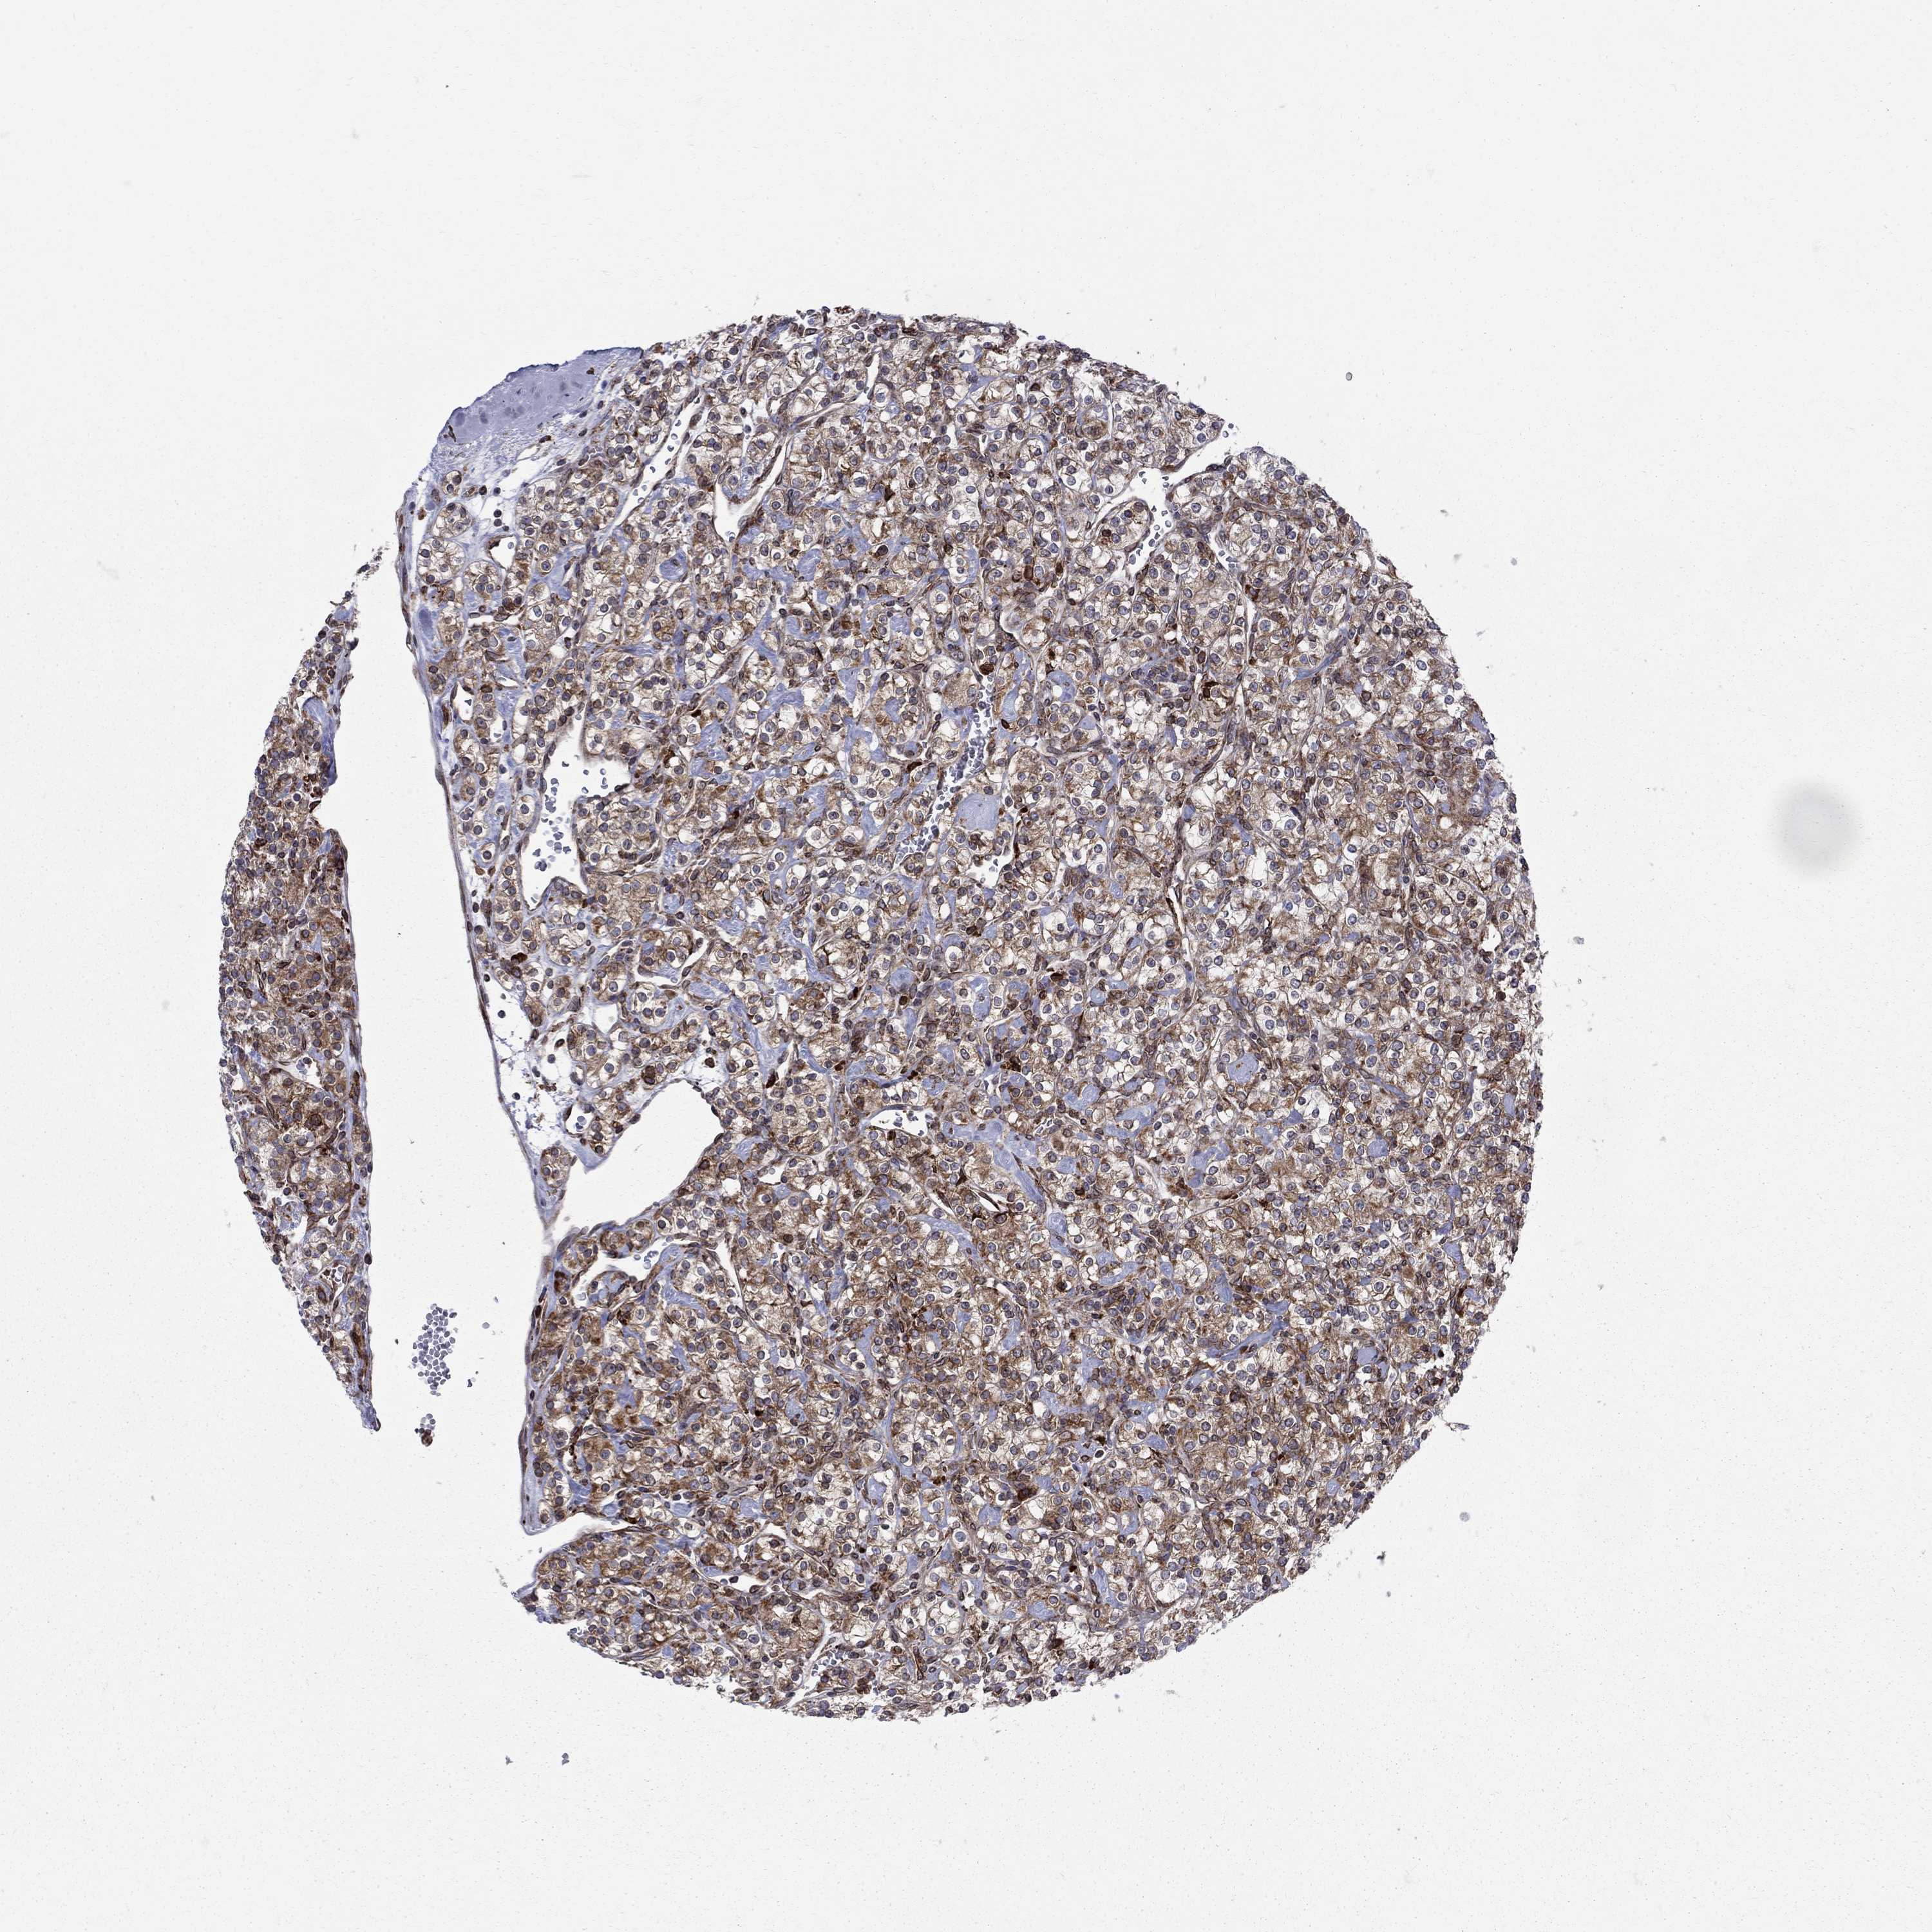

KIDNEY RENAL CLEAR CELL CARCINOMA (VALIDATION) - Interactive survival scatter ploti

The Survival Scatter plot shows the clinical status (i.e. dead or alive) for all individuals in the patient cohort, based on the same data that underlies the corresponding Kaplan-Meier plots. Patients that are alive at last time for follow-up are shown in blue and patients who have died during the study are shown in red.

The x-axis shows the expression levels (FPKM) of the investigated gene in the tumor tissue at the time of diagnosis. The y-axis shows the follow-up time after diagnosis (years). Both axes are complimented with kernel density curves demonstrating the data density over the axes. The top density plot shows the expression levels (FPKM) distribution among dead (red) and alive patients (blue). The right density plot shows the data density of the survived years of dead patients with high and low expression levels respectively, stratified using the cutoff indicated by the vertical dashed line through the Survival Scatter plot. This cutoff is automatically defined based on the FPKM cutoff that minimizes the p-score. The cutoff can be changed by dragging the vertical line or by entering a cutoff value in the square labeled "Current cut-off".

Under the Survival Scatter plot the p-score landscape (black curve; left axis) is shown together with dead median separation (red curve; right axis). Dead median separation is the difference in median mRNA expression between patients who have died with high and low expression, respectively. It is calculated as follows: median FPKM expression of dead patients with high expression - median FPKM expression of dead patients with low expression. This is intended to aid the user in visually exploring custom cutoffs and the associated p-scores and dead median separation.

Individual patient data is displayed and can be filtered by clicking on one or more of the category buttons on the top of the page. Categories describing expression level and patient information include: high, low, alive, dead, female, male and tumor stages. The scale of the x-axis can be toggled between linear and log-scale by clicking on the "x log" button. Mouse-over function shows TCGA ID, patient information and mRNA expression (FPKM) for each patient.

& Survival analysisi

Kaplan-Meier plots summarize results from analysis of correlation between mRNA expression level and patient survival. Patients were divided based on level of expression into one of the two groups "low" (under cut off) or "high" (over cut off). X-axis shows time for survival (years) and y-axis shows the probability of survival, where 1.0 corresponds to 100 percent.

CAB39L is not prognostic in Kidney Renal Clear Cell Carcinoma (validation)

Best expression cut offi

: 6.59

P scorei

N/A

Average pTPM 6.8

Number of samples 100